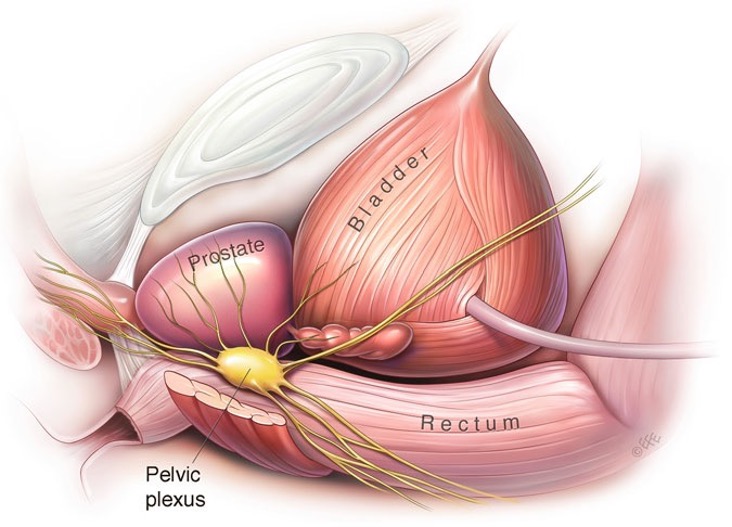

PROSTATECTOMIA ROBÓTICA

O tumor de próstata é o principal câncer que acomete ao homem, sendo de extrema importância o diagnóstico e tratamento precoces.

A PROSTATECTOMIA ROBÓTICA é uma técnica moderna e minimamente invasiva que utiliza uma plataforma robótica para melhorar a qualidade e precisão da cirurgia

DOENÇAS DA PRÓSTATA

Hiperplasia Prostática Benigna

Infecções da próstata (prostatite)

Câncer de Próstata